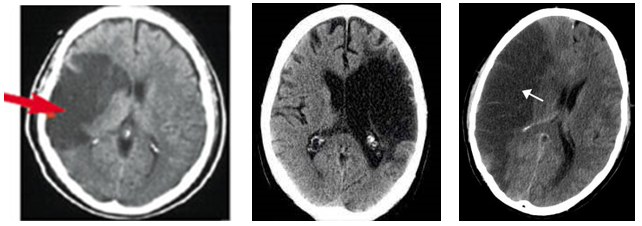

1) 뇌경색

뇌경색의 부위가 검게 나타난다. (저음영)

뇌경색은 발생한 후 24시간 이내에는 경색부위가 보이지 않는 경우가 많아 정상처럼 나타날 수 있다.

2) 뇌출혈

출혈 부분의 희게 나타난다. (고음영)

뇌출혈은 출혈 직후부터 CT에 고밀도로 나타난다.

반대로 뇌경색의 경우 1~2일 지나 CT 병변에서 나타난다. 급성기 뇌졸중에서 CT가 정상이면 뇌경색으로 진단 할 수 있다. 조기에 저음영화 되어버리므로 가능한 발병 후 빨리 찍는 것이 중요하다.